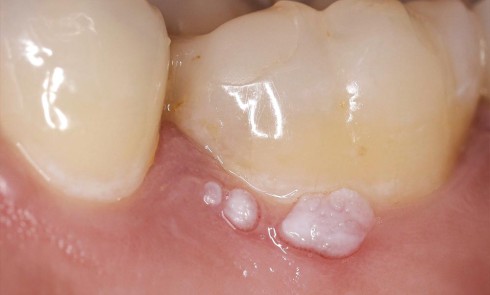

Article réservé à nos abonnés Image commentée : une petite boursouflure

Situation clinique Anamnèse. Une patiente âgée de 26 ans consulte sur les conseils de son chirurgien-dentiste traitant, lequel a remarqué...